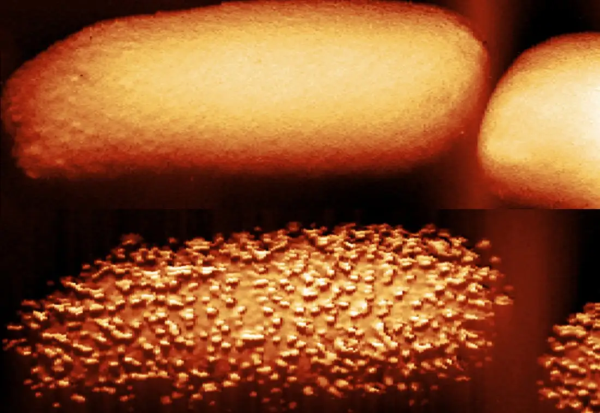

Фото: Nature Microbiology

Користејќи биохемиски тестови и атомски силен микроскоп, метода во која игла со големина од нанометар ја мапира површината на клетката, Едвардс и неговиот тим забележале дека полимиксинот B предизвикува испупчување на површината на бактеријата ешерихија коли. Неколку минути подоцна, бактериите го исфрлаат липополисахаридот. Во процесот, бактериите се обидуваат да ги надоместат изгубените липополисахариди со додавање нови.